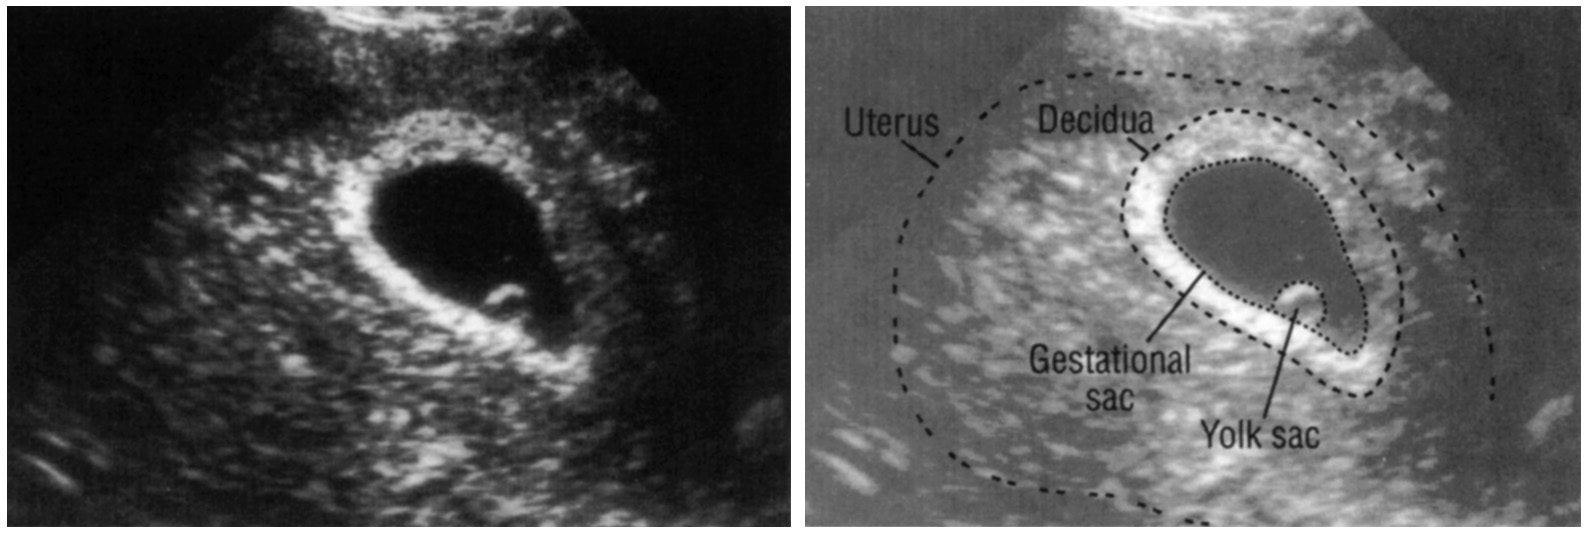

Плодный мешок узи

Плодный мешок узи 119 фотографий